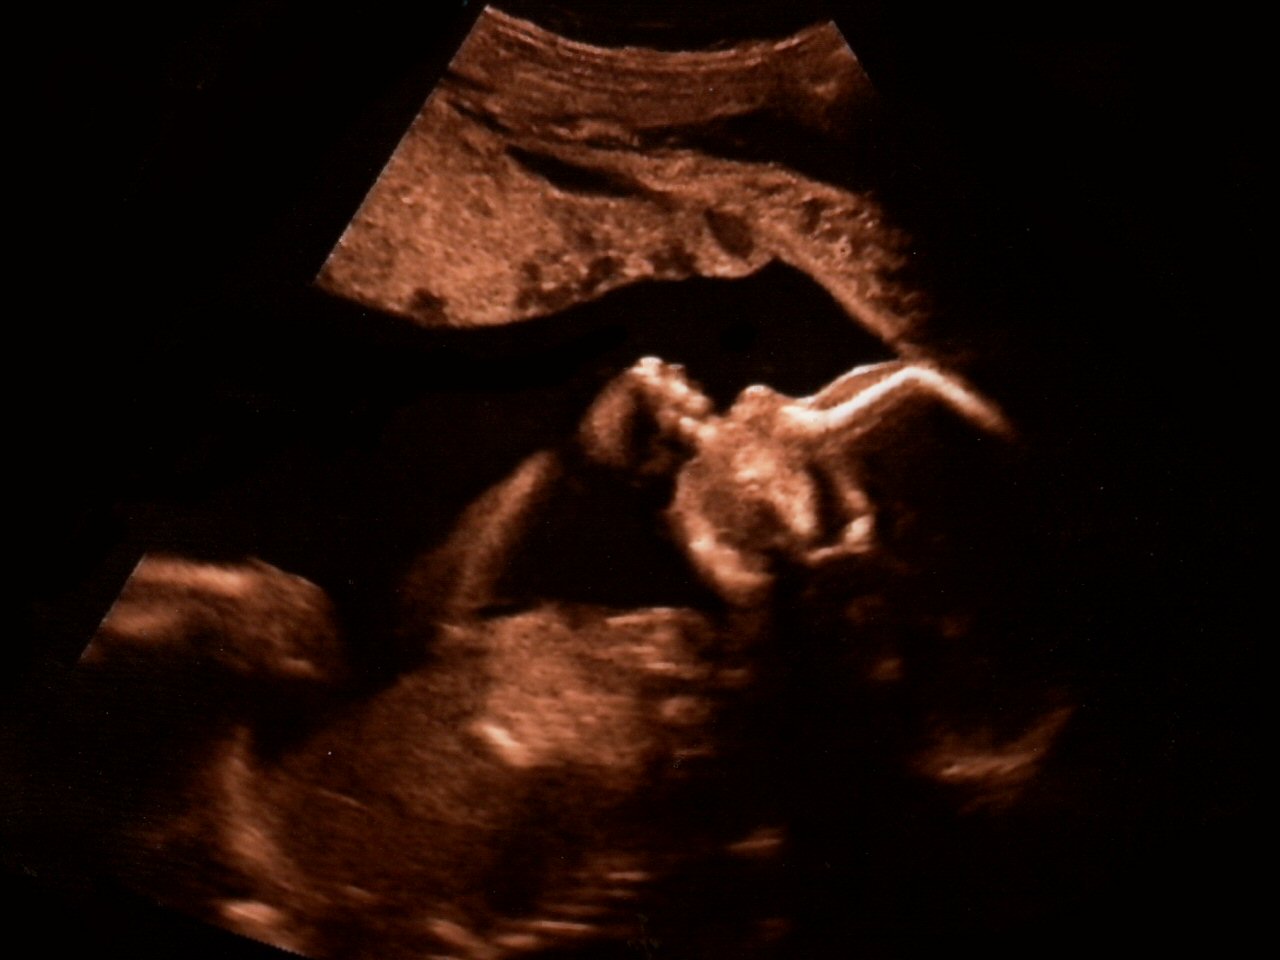

Una madre surrogata è stata obbligata dai genitori committenti ad abortire perché un’ecografia aveva rivelato che al bambino mancavano due dita. Lo riporta LifeSite,

«Dopo l’ecografia, si scoprì che al bambino mancavano due dita», ha raccontato Maurel. «E i genitori committenti non volevano un bambino con due dita mancanti, quindi chiesero alla madre surrogata di praticare un aborto». «Era al terzo trimestre di gravidanza. Devo dire: “una bambina già formata”», ha dichiarato Maurel.

La madre si è rifiutata. «Voleva tenere il bambino. Si è rifiutata (di abortire). Ha detto “no”», ha osservato Maurel. La madre surrogata, di cui non è stato rivelato il nome, è stata minacciata dagli avvocati dei genitori committenti.

«Purtroppo ha ricevuto una lettera dagli avvocati dei genitori committenti in cui si affermava che il contratto doveva essere rispettato e che lei doveva abortire, altrimenti non avrebbe ricevuto il denaro e… sarebbe stata citata in giudizio, quindi è stata costretta ad abortire questo bambino, solo perché gli mancavano due dita», ha detto Maurel.